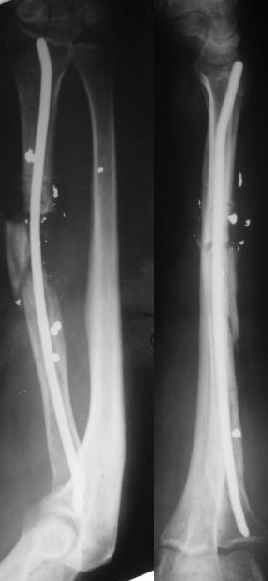

Re: Огнестрельный перелом луча

В приложении - снимок по окончании дистракции, и после смены аппарата на стержень (довольно толстый, 5 мм). С входом в канал на центральном отломке пришлось малость попотеть, промежуточный отломок его прикрывал. Но все-таки удалось закрыто проколупать. Надеюсь, дня через 3-4 после операции можно будет передать пациента нейрохирургам. Буду признателен за критику и комментарии.